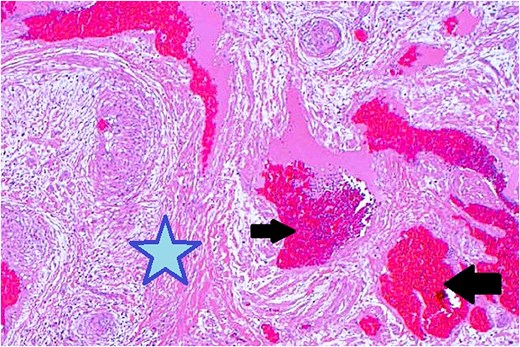

Surgical excision was performed via a subciliary approach, and the mass was removed entirely. Macroscopic examination revealed a 15 × 10 mm encapsulated tumor. Histology demonstrated interlacing bundles of smooth muscle cells surrounding thick-walled vascular channels without atypia, mitotic figures, or necrosis. Immunohistochemical staining was positive for smooth muscle actin (SMA) and desmin, confirming the smooth muscle origin of the tumor (Fig. 5).

Histopathological examination with hematoxylin and eosin staining shows muscular components (marked with a star) and vascular components (marked with arrows).

Histologically, the tumor showed typical features of angioleiomyoma: bundles of smooth muscle cells surrounding vascular channels without atypia or mitoses. Immunohistochemistry confirmed smooth muscle origin with positive staining for SMA and desmin. These findings exclude malignancy and other differential diagnoses such as hemangioma, schwannoma, or malignant soft tissue tumors [7].